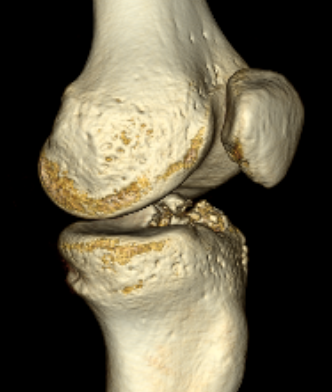

CT

Can help classify and thus guide treatment

Type II Type III

Type IV